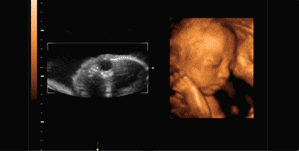

小丽的这件事引起了网友的热议,很多人批评小丽的老公不懂事,小孩的长相本来就变化得很快,健康才是最重要的,而且四维是一定要做的,除了能提前和宝宝见面,更为重要的是,四维彩超能够多方位、多角度地观察宫内胎儿的生长发育情况,为早期诊断胎儿先天性体表畸形和先天性心脏疾病提供准确的科学依据。也有网友晒出了自己宝宝做四维时的动态图,萌萌哒的小家伙不知多可爱。

多么活泼好动呀

四维彩超和二维、三维的区别

二维彩超为平面影像,三维彩超为立体静态影像,四维彩超为立体动态影像。四维彩超相比二维和三维彩超,清晰度和精准度更高。四维彩超排畸率较高。而且四维彩超可以将宝宝的动态刻录下来,方便父母观看。医生指出,四维彩超的最佳检查时间为孕22-28周,这段时期检查,胎儿活动度大,体表也比较丰满,有利于胎儿四维超声成像和胎儿畸形筛查,是排畸的最好时期。

喝奶技能从小学起

人家还要睡就不要拍了嘛!